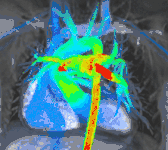

4D flow CMR

Conventional phase contrast imaging can be extended by applying flow-sensitive gradients in 3 orthogonal planes within a 3D volume throughout the cardiac cycle. Such 4D imaging encodes the velocity of flowing blood at each voxel in the volume enabling fluid dynamics to be visualised using specialist software. Applications are in complex congenital heart disease and for research into cardiovascular flow characteristics - however it is not in routine clinical use due to the complexity of post-processing and relatively long acquisition times.[25]